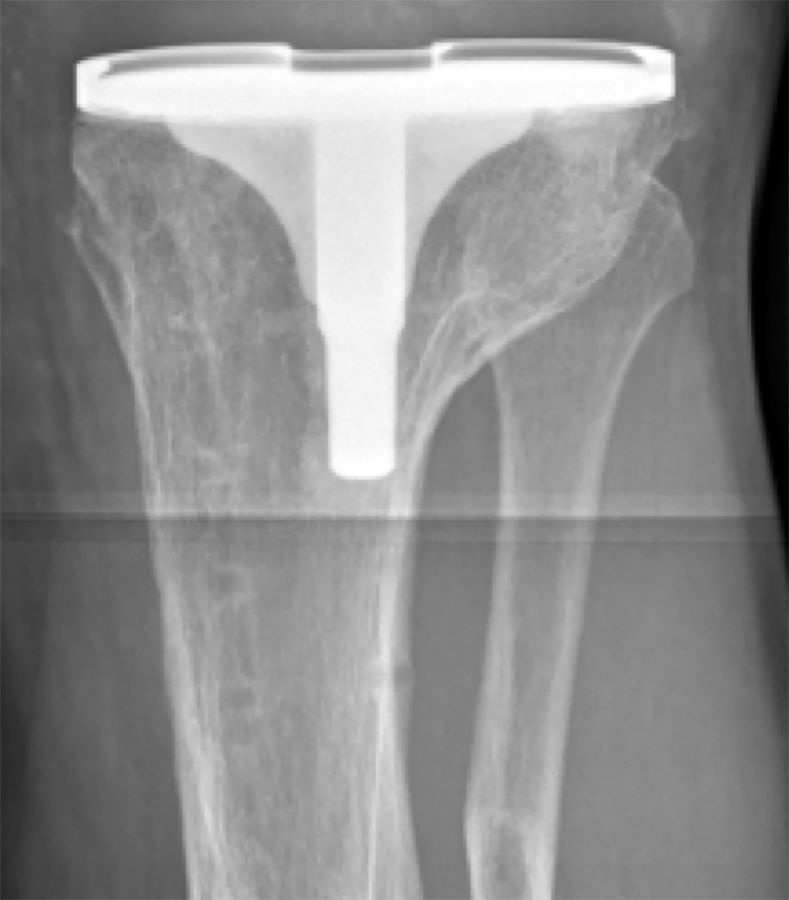

The risk of vascular injury and the difficulty of exposure is less when the femur is subluxated anterior, however, this situation is not without difficulties itself. Usually anterior subluxation of the femur on the tibia results in a significant flexion contracture and significant distal femur resection is needed to allow full extension of the knee and balance flexion and extension space. Based on my personal experience I strongly favor a hinge implant for posttraumatic anterior or posterior dislocations of the femur (Figure 5a, b, c, d).

My rational for this implant choice is that in severe anterior dislocation of the femur, often, the insertion of the collateral ligaments gets compromised when additional distal femur resection is needed to allow full extension. In addition, it is difficult to achieve reliable postoperative range of motion when encountering a knee subluxation in the presence of preoperative stiffness (less than 80 degrees arc of motion). Since the combination of a traumatic dislocation is seldom associated with an addition extraarticular deformity stemmed hinge implants can usually be used without problems.

4. I favor hinge implants for patients with anterior and posterior knee dislocations and an overall arc of motion of less than 80 degrees.